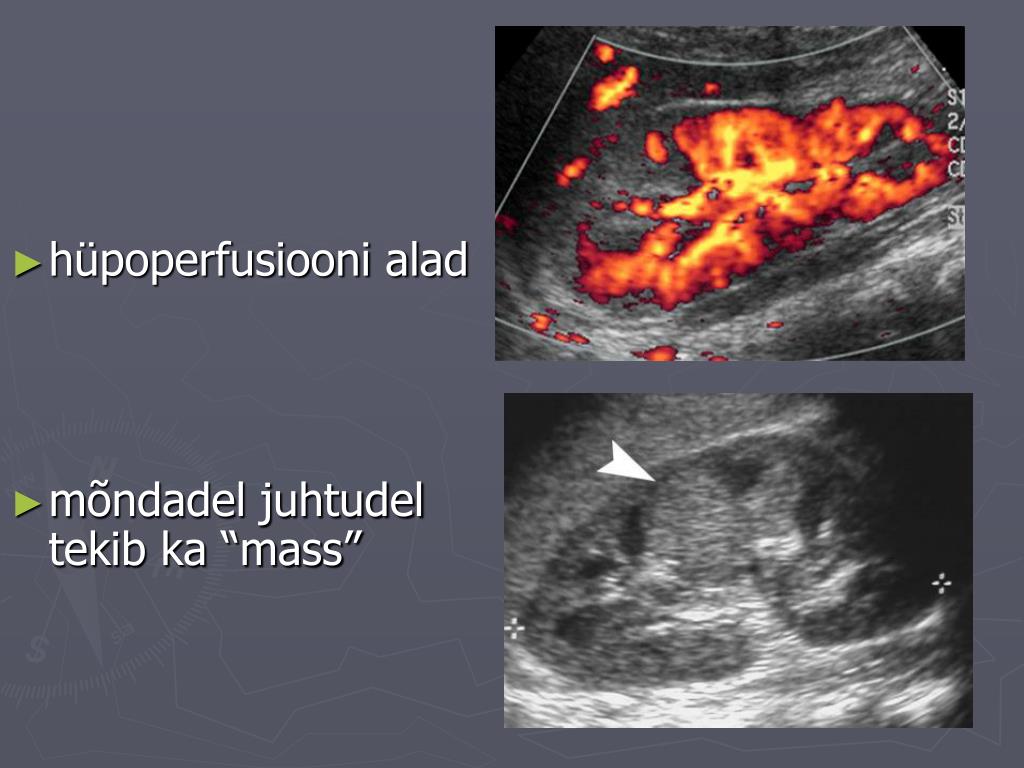

9. hüpoperfusiooni alad • mõndadel juhtudel tekib ka “mass”